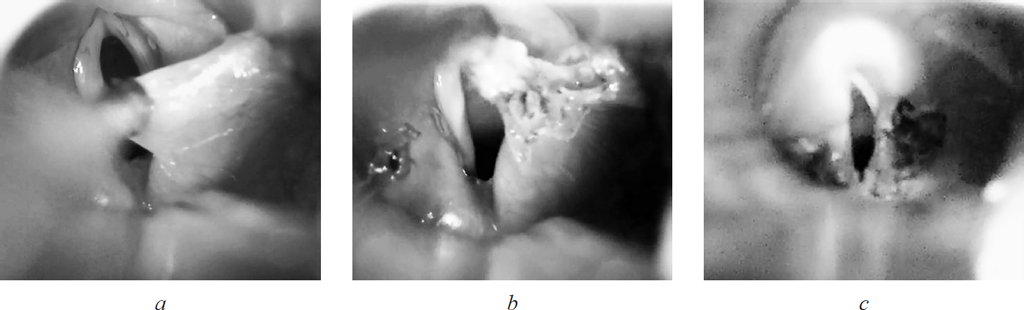

Ребенку была выполнена супраглоттопластика в объеме диссекции черпалонадгортанных складок и иссечения клиновидных хрящей (учитывая наличие клинико-эндоскопических признаков ларингомаляции 2-го типа) (рис. 3, а–с).

Рис. 3. Этапы супраглоттопластики (а–с). Клинок ларингоскопа установлен под корень языка

Сразу после операции отмечались купирование стридора, втяжения уступчивых мест грудной клетки. Девочка была выписана на 11-е сутки после оперативного лечения (рис. 4).

Рис. 4. Эндофотография гортани на 10-е сутки после супраглоттопластики. Сохраняется налет фибрина в области правой черпалонадгортанной складки